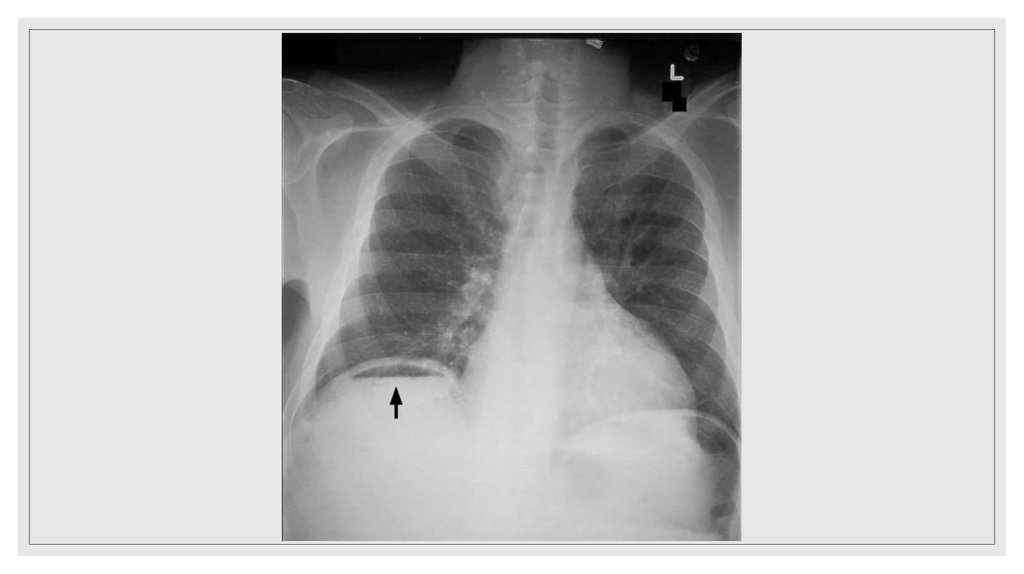

Гемоторакс

38. Гемоторакс

Классификация по Куприянову

◦ Малый гемоторакс – наличие крови ниже угла лопатки (до 500 мл).

◦ Средний гемоторакс – граница жидкости на уровне угла лопатки (до

1000 мл).

◦ Большой гемоторакс – до уровня II ребра (до 1500 мл).

◦ Тотальный гемоторакс – жидкость заполняет всю плевральную

полость.

39. Виды гемоторакса